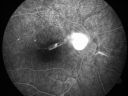

Toxocariasis1027 views15-year-old one year ago had pink eye then her vision has been abnormal. She recently went for a drivers’ test and failed, OD: 20/80; OS: 20/20.